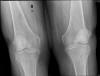

Prótesis completa bilateral de rodillas.